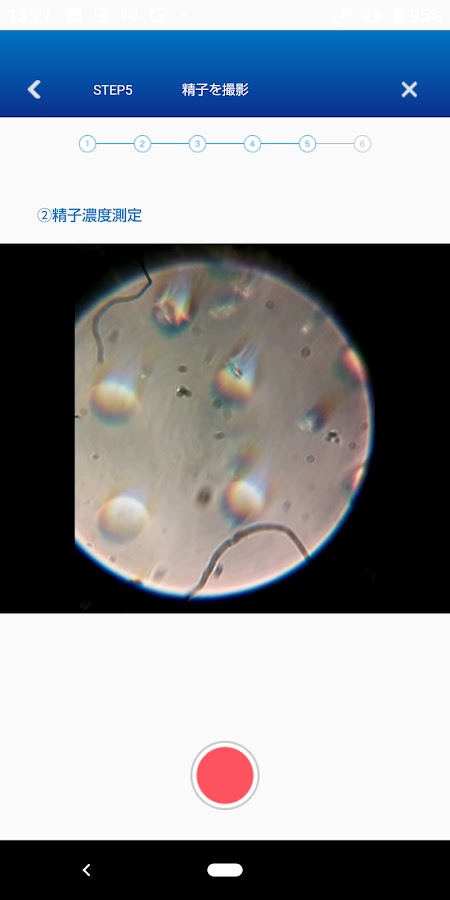

dotest! — приложение, которое позволяет легко и точно проверить концентрацию подвижных сперматозоидов в домашних условиях с помощью смартфона.

С помощью этого продукта можно подсчитать, сколько здоровых сперматозоидов (т. е. подвижных сперматозоидов) присутствует в образце.

*Этот продукт представляет собой простой набор, который проверяет концентрацию подвижных сперматозоидов на основе концентрации и скорости подвижности сперматозоидов в соответствии со стандартами тестирования сперматозоидов ВОЗ. Этот результат был рассчитан на основе стандартов ВОЗ и не предназначен для оценки способности спермы к оплодотворению.